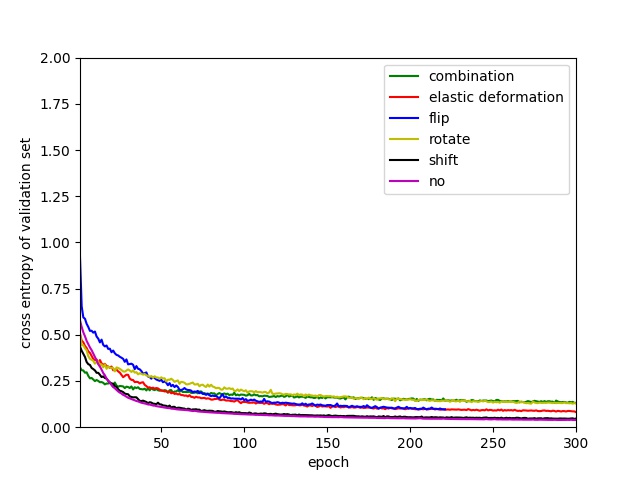

Data augmentation is a widely used technique to handle the overfitting issue caused by limited training samples. In image segmentation tasks, one can generate more images from one image using image transformation methods. The most common methods include rotation, flipping, shifting and rescaling. Elastic deformation transform, a higher level transformation method, is also employed in some image segmentation works. Ronneberger et al. [19] claim that elastic deformation is the key method to do data augmentation for a segmentation network with very limited annotated images.

However, to the best of our knowledge, there is no systematic study of the effectiveness of these image transformation methods for nuclei segmentation using a fully convolutional network. We compare different training processes using rotation, flipping, shifting, rescaling and elastic deformation transform to augment the training data. To make fair comparisons, we let the training set and validation set have similar appearances by splitting each whole image into two sub-images and placing one in the training set and another one in the validation set. We randomly extract 6000 patches from the training set to train our neural networks and 6000 patches from the validation set for validation. The setting of these transformation methods is same with those reported in section II-C2. The comparison is shown in Fig.10(b). ’no’ means don’t apply data augmentation. ’combination’ means data augmentation is performed by combining elastic deformation, flip, rotate, shift and rescale. It is very clear that without data augmentation, the network has severe overfitting issue, validation loss starts to increase rapidly from epoch 5. Unexpectedly, rotating rather than elastic deformation has achieved the best performance in performance improvement. But only rotating operation still cannot prevent the overfitting. One has to combine all of these transform methods together to do data augumentation to get good performance as done in this paper.